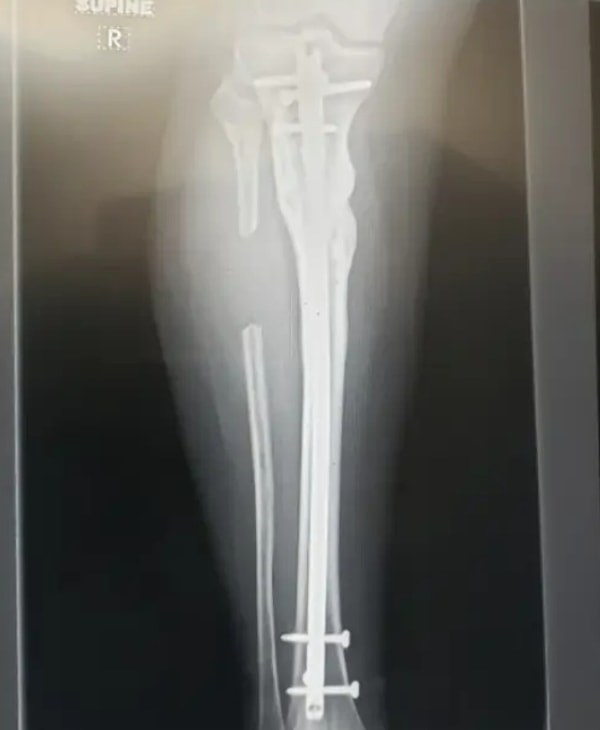

5. «Вокруг этого снимка собрались все врачи клиники, и никто не мог понять, куда делась часть моей малоберцовой кости»